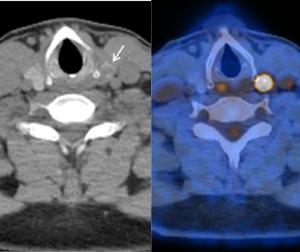

Comparative Study Shows Merits of PSMA PET/CT for Local Staging of Intermediate and High-Risk PCa